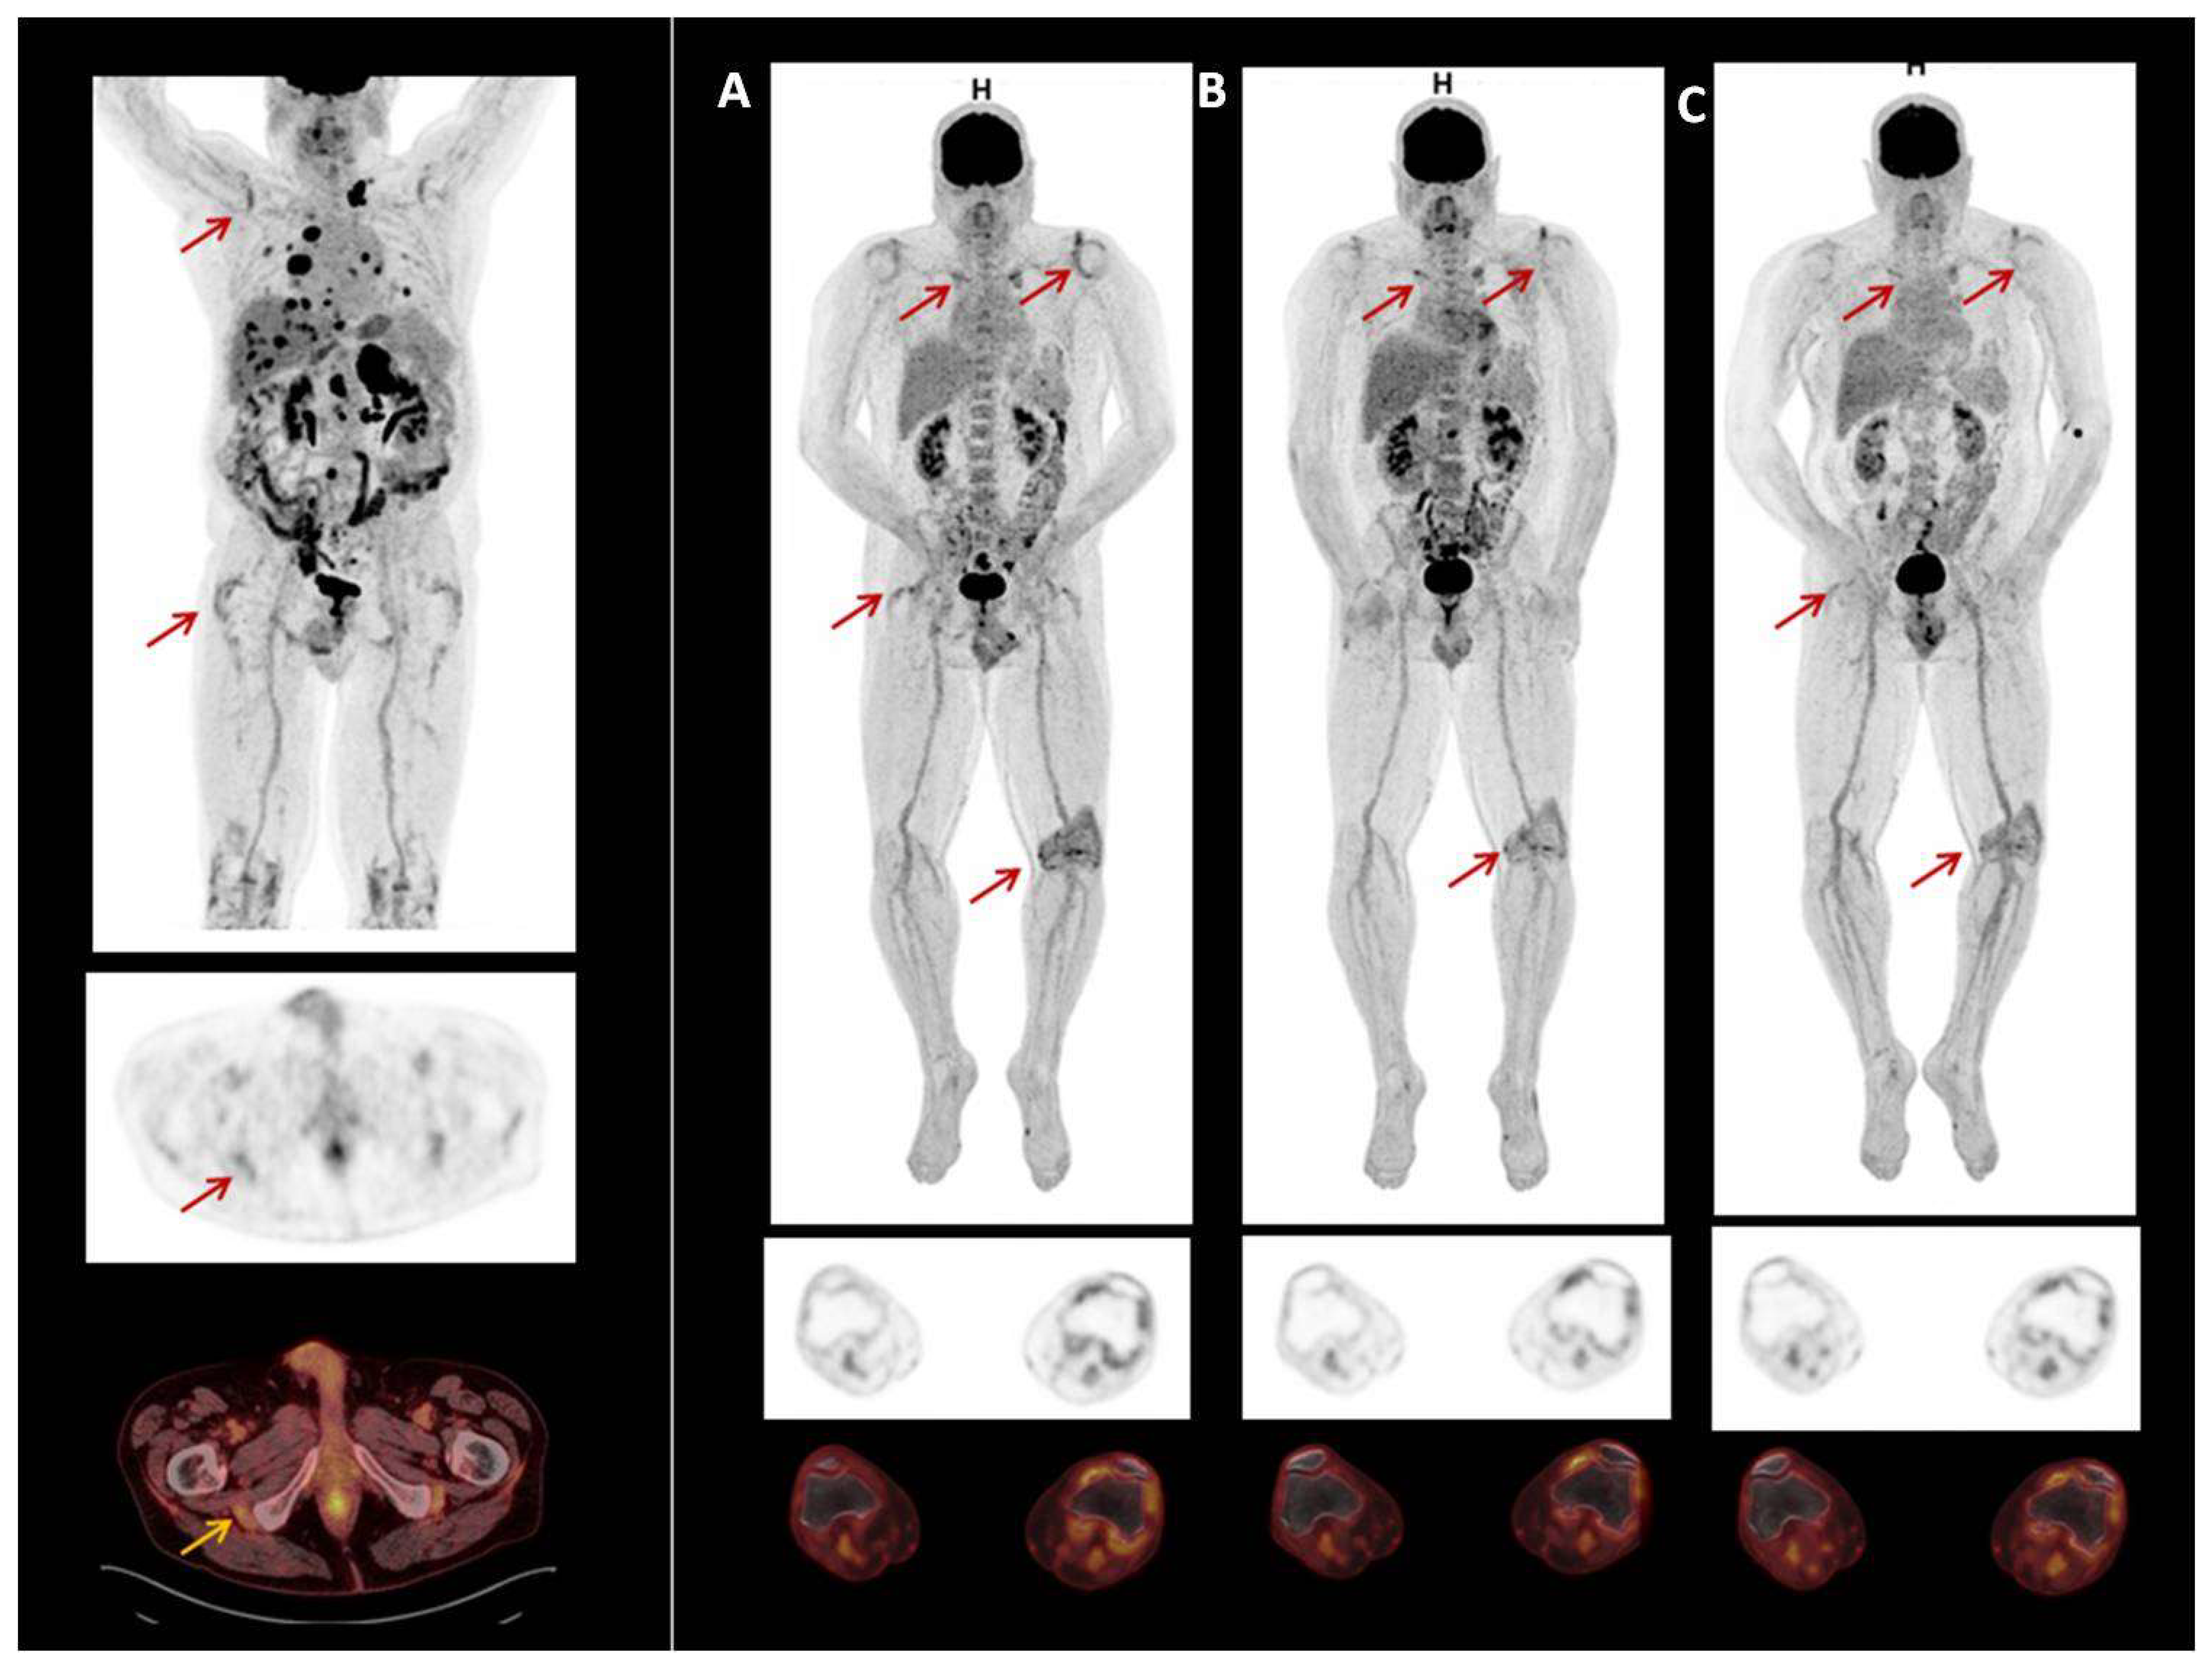

Two male patients had PET/CT scans to study rheumatic irAE secondary to the use of ICI. Patient 1 had melanoma and was treated with Pembrolizumab. Patient 2 had prostate carcinoma and was treated with Atezolizumab and Cabozantinib. Neither had previous rheumatic disease. Both patients presented clinical PMR. PET-CT scans showed symmetric FDG uptake in the shoulder, hip joints, and greater trochanter and ischial tuberosities. One also showed FDG uptake in the left knee (Figure 6). The previous and our reports of PET/CT scan findings in rheumatic irAEs are shown in Supplementary Table S2.

Figure 6.

18F-FDG PET/CT image of patient with prostate carcinoma treated with Atezolizumab and Cabozatinib. Symmetric FDG uptake shoulder, hip joints, greater trochanter and ischial tuberosities. Also show, FDG uptake in left knee (A). In 2020, due to irAEs ICI were discontinued. After discontinuation of treatment, uptake decreased (B,C).

Interestingly, some patients who underwent 18F-FDG PET before ICI therapy had some articular irAE-specific changes, which were exacerbated after immunotherapy [25,26,27,40]. As suggested by van der Geest et al., we agree that although this mild metabolic activity may also be seen in non-inflammatory conditions, it could suggest that low-grade, subclinical inflammation may already have been present at these sites before ICI therapy and was potentiated after treatment [26]. Inflammatory changes in multiple joints found by PET/CT in patients in this study probably reflected an autoimmune cellular attack on the synovia [28]. Here we report two consecutive patients with ICI-induced arthritis who presented PMR-like disease with 18F-FDG PET/CT showing symmetric FDG uptake in the shoulder, hip joints, greater trochanter, and ischial tuberosities, in accordance with the clinical signs.

18F-FDG PET has also high sensitivity in determining the resolution of inflammation, which is essential in the management of patients starting glucocorticoid treatment and interrupting or withdrawing ICI treatment. It has been found that, after discontinuation of immunotherapy and treatment with glucocorticoids, the changes found on PET were resolved [25,27,28]. Early detection of irAEs allows early management. Physicians should be aware of these irAEs when interpreting 18F-FDG PET in patients undergoing ICI therapy. Careful analysis of 18F-FDG PET-CT, focusing on the detection of signs of rheumatic irAEs could potentially help oncologists during follow-up who should request a prompt assessment by rheumatologists.